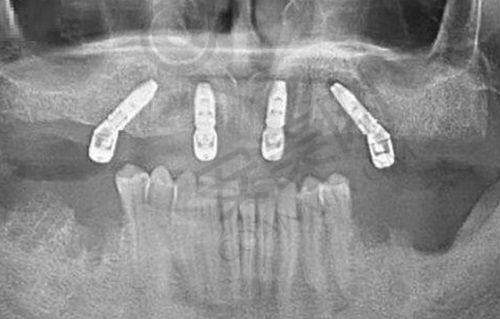

种植牙是郑州白皮书口腔医院的核心优势项目。在技术团队方面,由郑创益医生领衔,他擅长All - on - 4/6半口种植、穿颧穿翼等高难度技术。医院采用瑞士ITI、瑞典Active、韩国DIO、美国3i、德国SKY等主流种植体,支持即刻负重技术,单颗种植手术时间可缩短至30分钟。在设备上,医院配备了精良的数字化设备,如3D口腔扫描仪、数字化种植系统、口腔CT等,误差控制在0.1毫米内,还引入了UNIC咬合重建系统,支持复杂病例的数字化方案设计。通过三维模型进行可视化设计,医生可以清晰地看到患者的口腔结构和牙齿缺失情况,从而制定出更加精细的种植方案。这种技术不仅能避开重要的解剖结构,如血管、神经等,降低手术风险,还能使植入位置、角度和深度更加精细,实现微创操作,大大缩短手术时间和修复周期。无论是简单的单颗牙缺失,还是复杂的全口牙列缺损,医院都能凭借精良的技术和专精的医生团队,为患者提供高质量的种植服务。

走进郑州白皮书口腔医院,您会被其优雅舒适的环境所吸引。医院是独栋四层建筑,占地面积3000多平方米,内部环境整洁有序。设有23个标准化独立诊室,为患者提供了私密、安静的治疗空间,让患者在就诊过程中能够放松心情。医院还配备了现代化的数字化诊疗设备,如3D口腔扫描仪,它可以快速、精细地获取口腔三维模型,为种植修复等治疗提供正确的依据;口腔CT则能提供高分辨率的口腔影像,帮助医生精细诊断口腔疾病;数字化种植系统误差控制在0.1毫米内,实现了诊断与微创治疗的理想结合;此外,还有高精度牙冠制作设备、口腔消毒设备等,确保患者在舒适的环境下接受高质量的治疗。同时,医院在设计建造时大胆采用无障碍视觉空间,院内重中之重的消控中 心采用全透明玻璃墙和内部传输通道,患者路过时可以清晰看到消毒步骤有条不紊地进行,消毒到位,让患者就诊更放心。